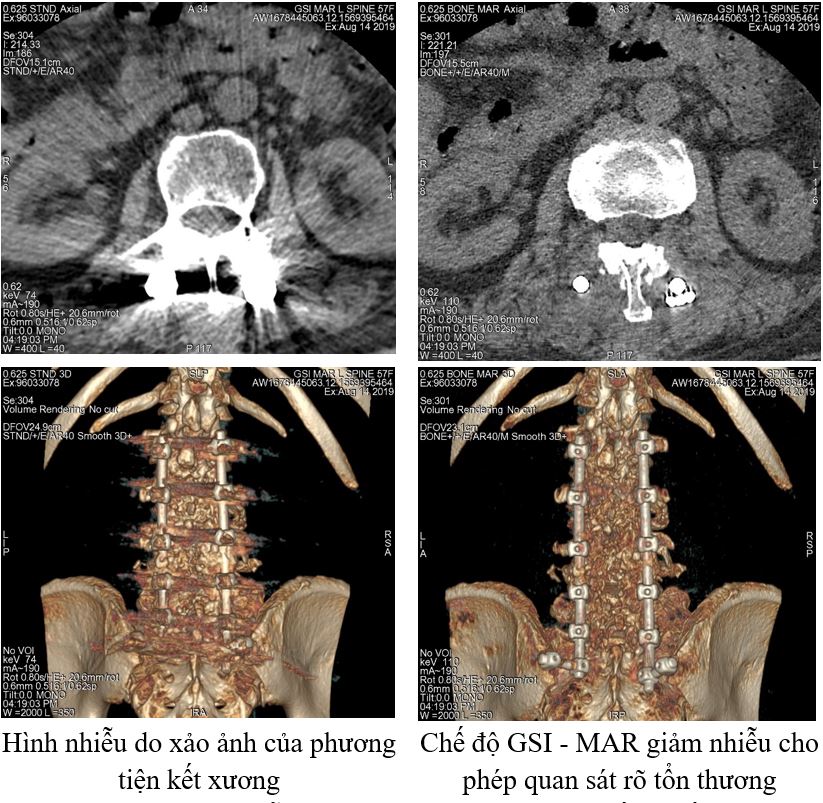

7. Giảm nhiễu do xảo ảnh các phương tiện kết xương bằng kim loại, các stent nội mạch, coil nút túi phình động mạch, mảng bám vôi hóa động mạch...

Hình ảnh giảm nhiễu do xảo ảnh của nẹp vít cột sống thắt lưng.